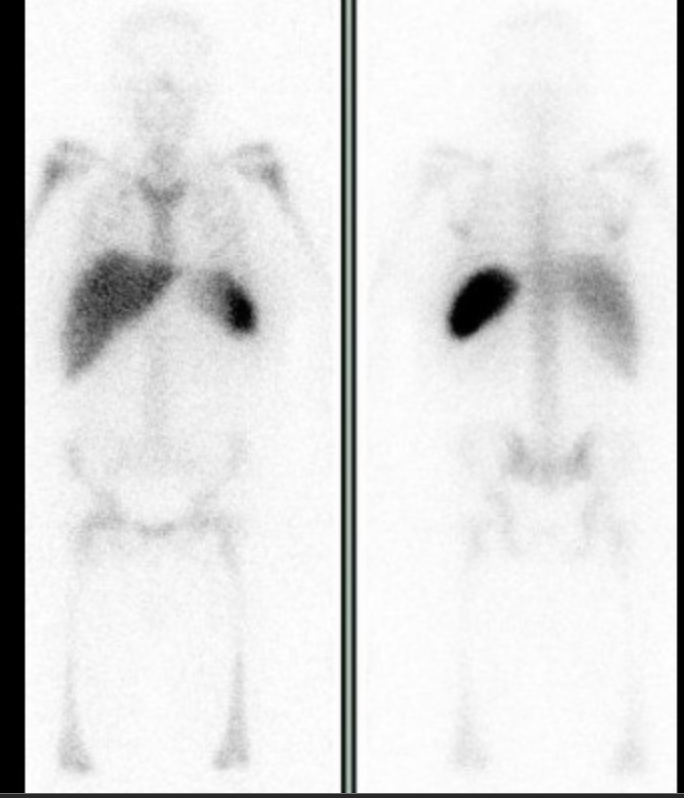

Inflammatory bowel disease

• In-WBC can be used in diagnosis of IBD

• Need to scan early (1-2 hours) when doing this because the labeled cells will get sloughed off from the focal site of active inflammation and mimic pan-colitis or multifocal sites of inflammation